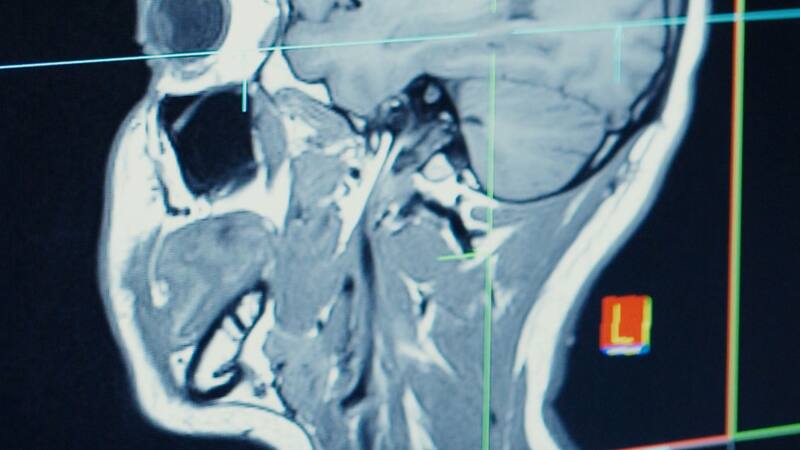

Estudio revela que luego de contagiarse de Covid el cerebro humano puede disminuir de tamaño

La investigación realizada advierte que existe una disminución de la materia gris en las regiones relacionadas con el olfato y la memoria.